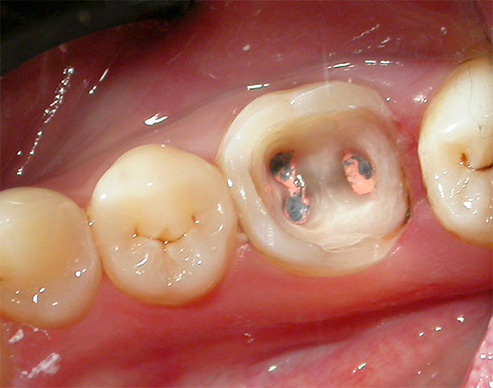

Le foto seguenti mostrano un esempio di carie nascoste in un dente sotto un ripieno:

Le immagini seguenti mostrano esempi di preparazione di cavità: